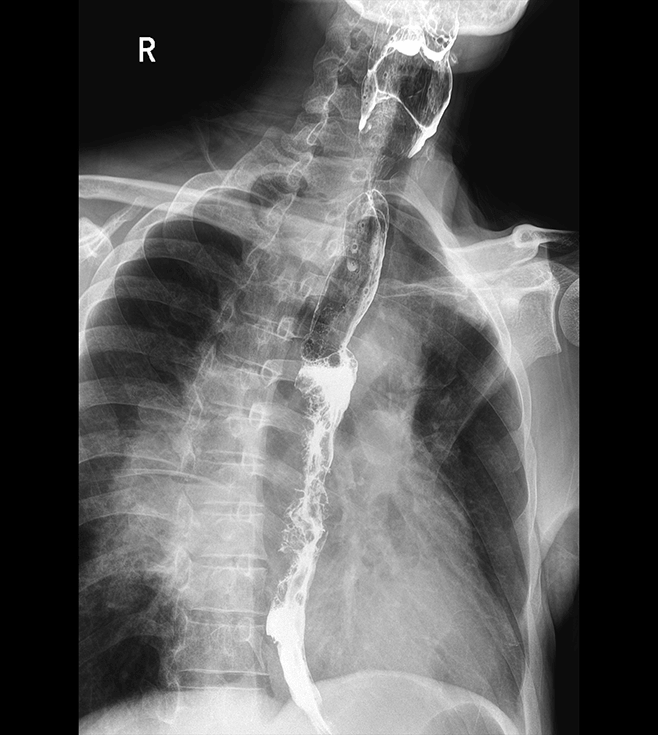

多功能诊断专用动态DR

太阳成集团tyc122cc入口科技全新设计的第四代床式动态DR,集拍片、透视、造影、全身拼接、尘肺体检于一体,一机多能,真正意义上实现全科室应用,提升医院实际效益。

多功能诊断应用专业设计

从医疗机构放射科的实际应用出发,针对多功能诊断进行多维度专业设计,优化病人检查体验,大幅提升操作技师工作效率。

高清动态平板探测器

搭载自主研发超清大视野动态平板探测器,600微米碘化铯大幅提升X线转化效率,独特的非晶硅阵列与高速读取集成电路紧密协作,轻松实现多帧率透视与高清点片。

专业的影像处理系统

“腾灵”系列搭载的IEAE影像处理系统,具备多项发明专利。本系统采用多频域图像处理技术,其6大核心处理模块使影像具有优秀的一致性、柔和性、空间层次感和纹理细腻度,为用户精准诊断病灶奠定了坚实的基础。